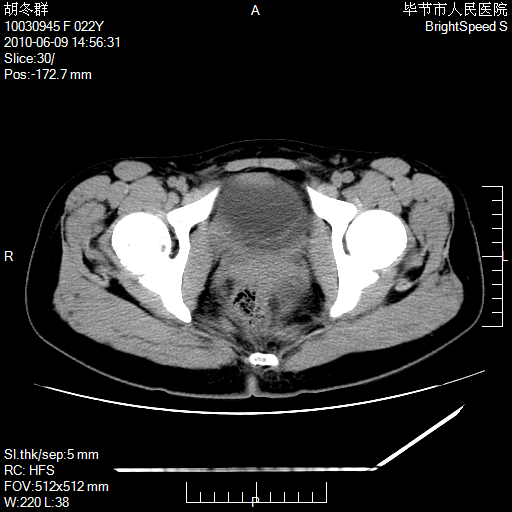

患者23岁,发现腹部包块3月。

盆腔内囊性占位;穿刺或者直接手术拿掉即可,不必紧张。

左侧卵巢囊腺瘤或囊腺癌

盆腔内囊性占位性病变;考虑左侧卵巢囊腺瘤。

有分隔、壁薄,支持考虑左侧卵巢囊腺瘤。

左侧卵巢浆液性囊腺瘤。

支持考虑左侧卵巢囊腺瘤;宫腔积液。

有分隔、壁薄,支持考虑左侧卵巢囊腺瘤。排尿后,膀胱缩小,由于重力作用,肿块下移就到了膀胱位置,很好理解。